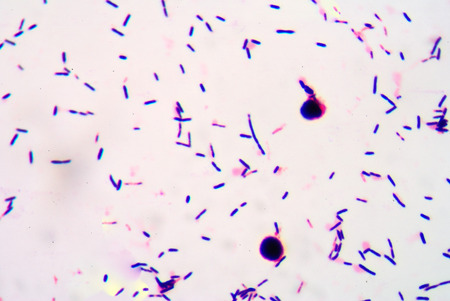

Title: showing title: microscopic view of purple rodshaped bacteria and circular microorganisms in dark background. resolution use.

gram stian was show gram positive bacilli.

Dense Clumps of Rod-Shaped Bacteria (Bacilli) Under a Microscope